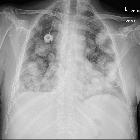

Cannonball metastases refer to multiple large, well-circumscribed, round pulmonary metastases that appear not unsurprisingly like cannonballs. The French terms "envolée de ballons" and "lâcher de ballons", which translate to "balloons release", are also used to describe this same appearance.

Metastases with such an appearance are classically secondary to :